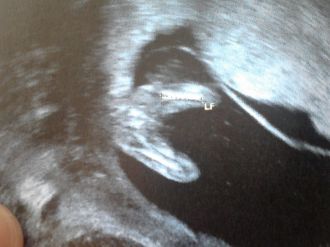

Lancement des pronostic sexe

Voila daprès le calendrier chinois ce serait un garçon! d'après l'écho le papa dit un garçon lol et vous??

petite foto de mesure du fémur c'est là que papa crois voir quelque chose!!!

garçon: 4

fille: 0